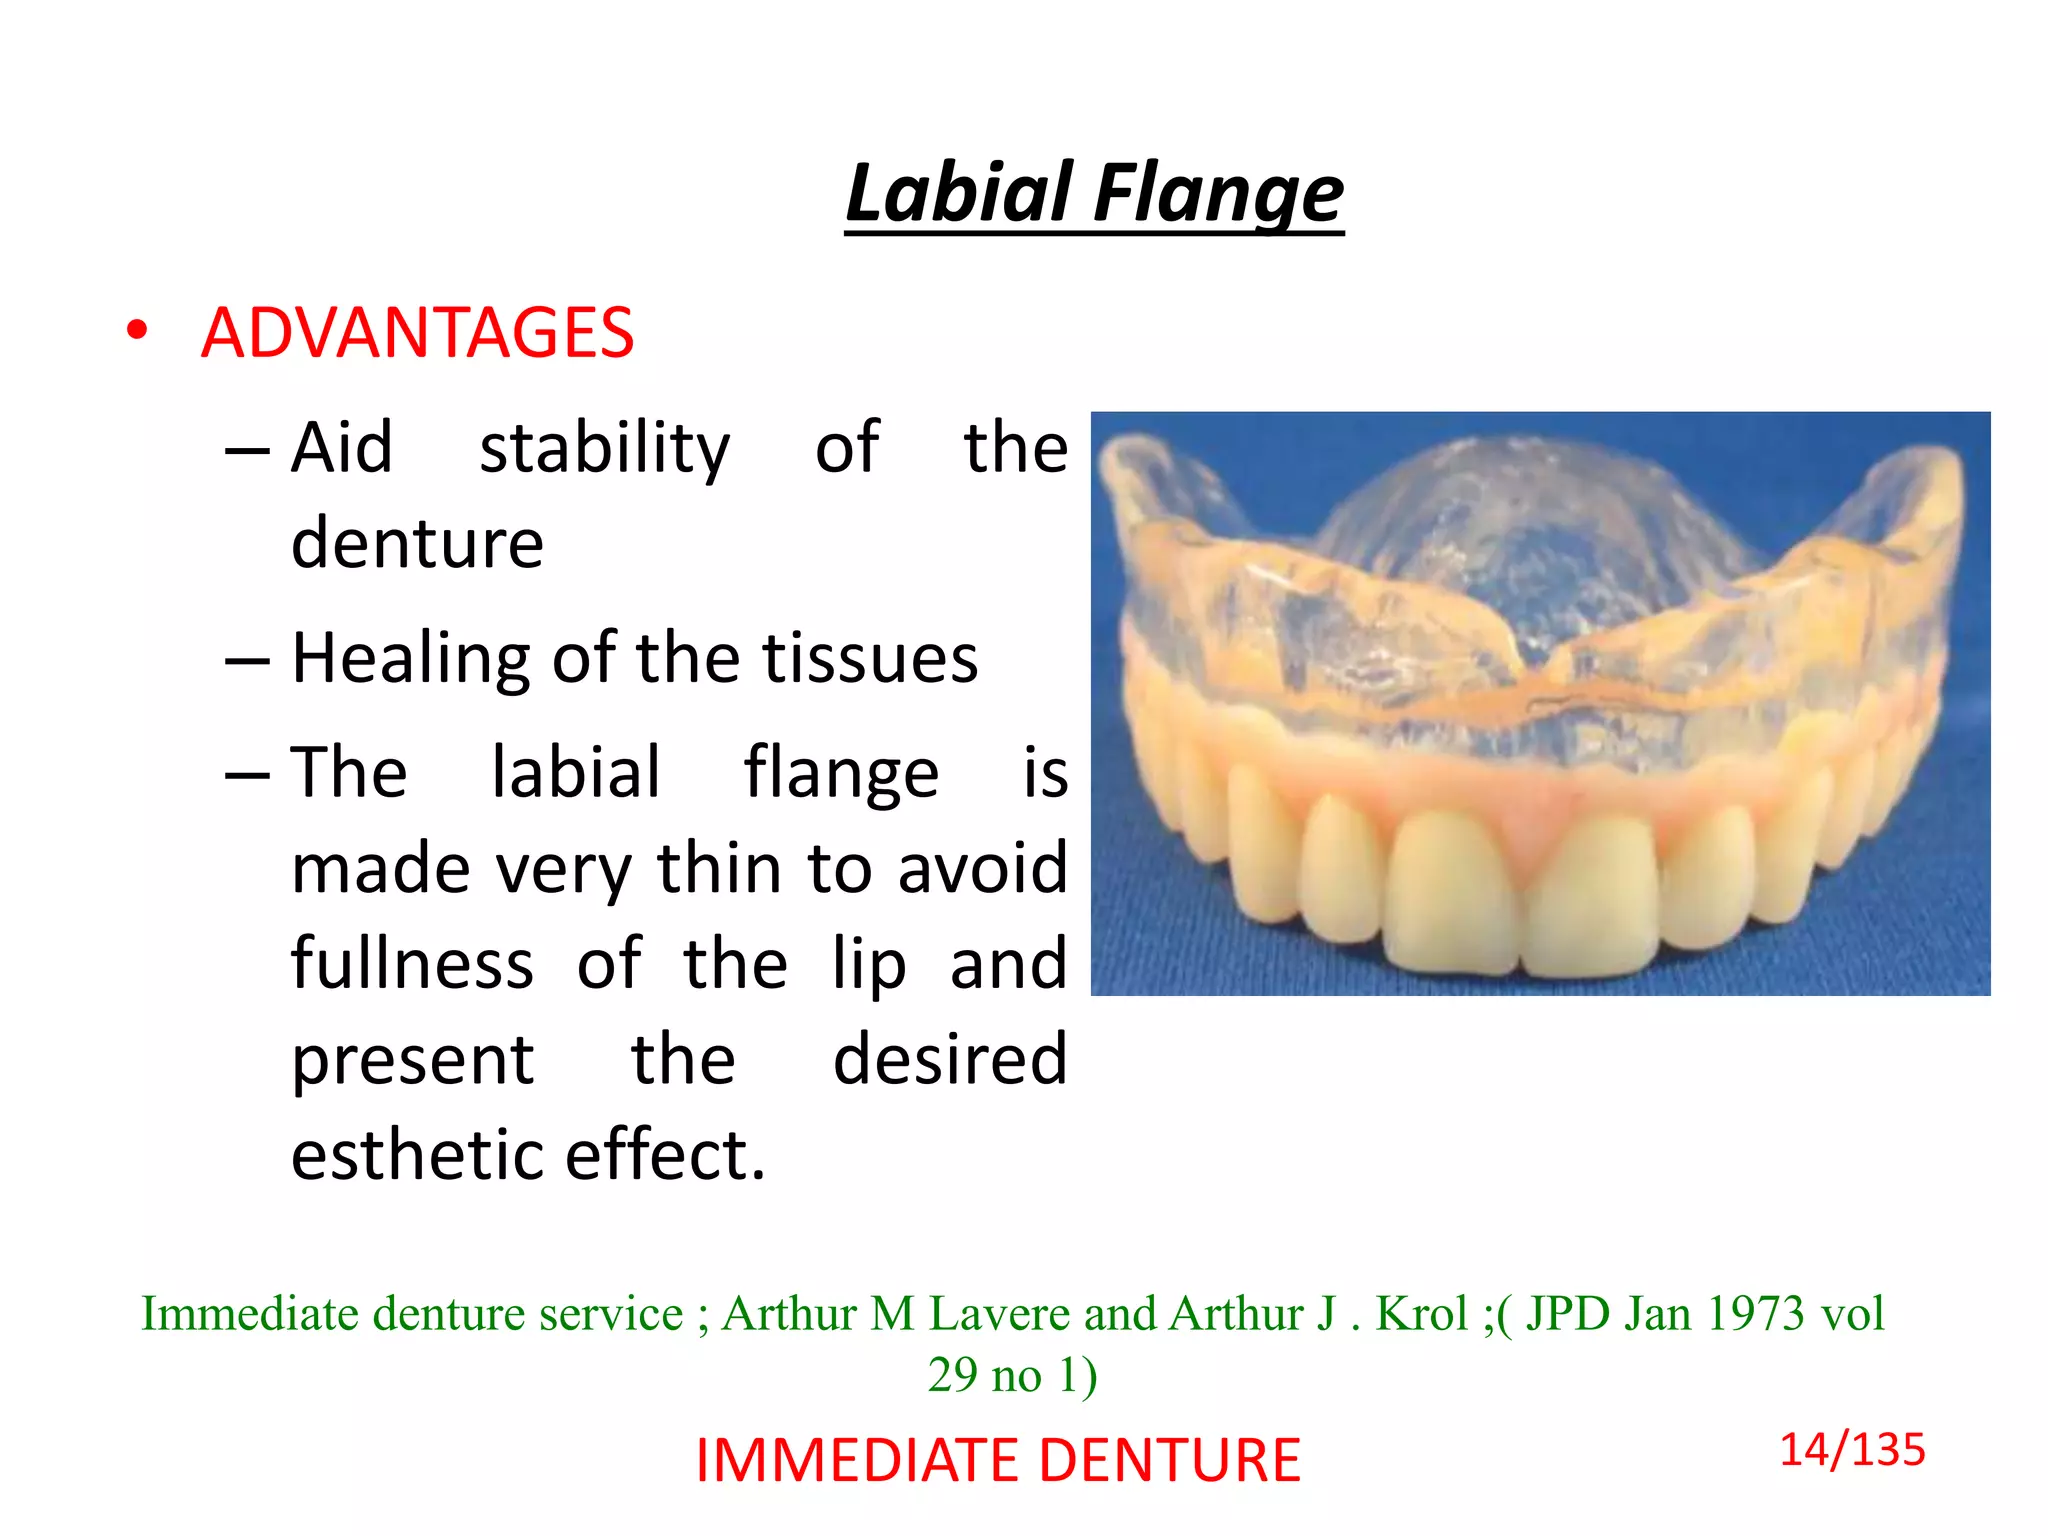

The document discusses immediate dentures, which are dentures fabricated and inserted immediately following tooth extraction. It describes the different types of immediate dentures, including conventional/classic immediate dentures, interim immediate dentures, labial flange dentures, partial flange dentures, and flangeless/socketed dentures. The advantages of immediate dentures include maintaining a patient's appearance without teeth, providing a bandage effect to extraction sites, and allowing easier adaptation to dentures during healing. However, immediate dentures also present challenges like reduced retention from undercuts caused by remaining posterior teeth.